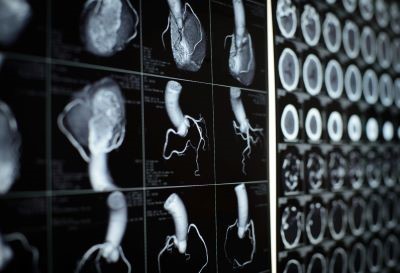

التصوير المقطعي المحوسب CT

يشير مصطلح " التصوير المقطعي المحوسب " أو CT إلى إجراء تصوير بالأشعة السينية باستخدام الكمبيوتر حيث يتم توجيه شعاع ضيق من الأشعة السينية إلى المريض وتدويره بسرعة حول الجسم، مما ينتج عنه إشارات تتم معالجتها بواسطة كمبيوتر الجهاز لتوليد صور مقطعية أو "شرائح". تسمى هذه الشرائح صورًا مقطعية ويمكن أن تعطي الطبيب معلومات أكثر تفصيلاً من الأشعة السينية التقليدية. بمجرد جمع عدد من الشرائح المتتالية بواسطة كمبيوتر الجهاز، يمكن "تكديسها" رقميًا معًا لتكوين صورة ثلاثية الأبعاد (3D) للمريض تسمح بتحديد أسهل للهياكل الأساسية وكذلك الأورام أو التشوهات المحتملة.<br /><br />متى يجب أن أحصل على فحص التصوير المقطعي المحوسب؟<br /><br />يمكن استخدام التصوير المقطعي المحوسب لتحديد الأمراض أو الإصابات في مناطق مختلفة من الجسم. على سبيل المثال، أصبح التصوير المقطعي المحوسب أداة فحص مفيدة للكشف عن الأورام أو الآفات المحتملة داخل البطن. يمكن طلب إجراء فحص التصوير المقطعي المحوسب للقلب عند الاشتباه في أنواع مختلفة من أمراض القلب أو التشوهات. يمكن أيضًا استخدام التصوير المقطعي المحوسب لتصوير الرأس من أجل تحديد الإصابات والأورام والجلطات التي تؤدي إلى السكتة الدماغية والنزيف وغيرها من الحالات. يمكنه تصوير الرئتين من أجل الكشف عن وجود أورام وانسداد رئوي (جلطات دموية) وسوائل زائدة وحالات أخرى مثل انتفاخ الرئة أو الالتهاب الرئوي. يعد التصوير المقطعي المحوسب مفيدًا بشكل خاص عند تصوير كسور العظام المعقدة أو المفاصل المتآكلة بشدة أو أورام العظام لأنه عادةً ما ينتج تفاصيل أكثر مما يمكن تحقيقه باستخدام الأشعة السينية التقليدية.<br /><br /><br />ما هو عامل التباين في التصوير المقطعي المحوسب؟<br /><br /><br /><br />كما هو الحال مع جميع الأشعة السينية ، يمكن تصوير الهياكل الكثيفة داخل الجسم - مثل العظام – بسهولة، في حين تختلف الأنسجة الرخوة في قدرتها على إيقاف الأشعة السينية وبالتالي قد تكون باهتة أو يصعب رؤيتها. لهذا السبب، تم تطوير عوامل التباين التي تكون مرئية للغاية في الأشعة السينية أو التصوير المقطعي المحوسب وهي آمنة للاستخدام في المرضى. تحتوي عوامل التباين على مواد يمكنها إيقاف الأشعة السينية وبالتالي تكون أكثر وضوحًا في صورة الأشعة السينية. على سبيل المثال، لفحص الجهاز الدوري، يتم حقن عامل تباين وريدي (IV) يعتمد على اليود في مجرى الدم للمساعدة في إضاءة الأوعية الدموية. يستخدم هذا النوع من الاختبار للبحث عن العوائق المحتملة في الأوعية الدموية، بما في ذلك تلك الموجودة في القلب. تُستخدم عوامل التباين الفموية، مثل المركبات القائمة على الباريوم، لتصوير الجهاز الهضمي، بما في ذلك المريء والمعدة والجهاز الهضمي.<br /><br /><br /><br />هل هناك مخاطر؟<br /><br />يمكن لفحوصات التصوير المقطعي المحوسب تشخيص الحالات التي قد تهدد الحياة مثل النزيف أو جلطات الدم أو السرطان. يمكن أن يكون التشخيص المبكر لهذه الحالات منقذًا للحياة. ومع ذلك، تستخدم فحوصات التصوير المقطعي المحوسب الأشعة السينية ، وتنتج جميع الأشعة السينية إشعاعًا مؤينًا . للإشعاع المؤين القدرة على التسبب في تأثيرات بيولوجية في الأنسجة الحية. وهذا خطر يزداد مع عدد مرات التعرض على مدار حياة الفرد. ومع ذلك، فإن خطر الإصابة بالسرطان من التعرض للإشعاع السينية صغير بشكل عام.<br /><br /><br /><br />لا يشكل التصوير المقطعي المحوسب لدى المرأة الحامل أي مخاطر معروفة على الجنين إذا لم تكن منطقة الجسم التي يتم تصويرها هي البطن أو الحوض. بشكل عام، إذا كانت هناك حاجة إلى تصوير البطن والحوض، يفضل الأطباء استخدام الفحوصات التي لا تستخدم الإشعاع، مثل التصوير بالرنين المغناطيسي (MRI) أو الموجات فوق الصوتية . ومع ذلك، إذا لم يتمكن أي منهما من تقديم الإجابات المطلوبة، أو كانت هناك حالة طارئة أو قيود زمنية أخرى، فقد يكون التصوير المقطعي المحوسب خيارًا بديلًا مقبولًا للتصوير.<br />قد تسبب عوامل التباين في بعض المرضى تفاعلات حساسية، أو في حالات نادرة، فشل كلوي مؤقت. لا ينبغي إعطاء عوامل التباين الوريدي للمرضى الذين يعانون من خلل في وظائف الكلى لأنها قد تسبب انخفاضًا إضافيًا في وظائف الكلى، والذي قد يصبح دائمًا في بعض الأحيان.<br /><br />نظرًا لأن الأطفال أكثر حساسية للإشعاع المؤين وطول العمر المتوقع لديهم، فإنهم يواجهون خطرًا نسبيًا أعلى للإصابة بالسرطان بسبب هذا الإشعاع مقارنة بالبالغين. قد يرغب الآباء في سؤال فني التكنولوجيا أو الطبيب عما إذا كانت إعدادات أجهزتهم قد تم تعديلها لتناسب الأطفال.<br /><br />ما هي أمثلة المشاريع الممولة من NIBIB باستخدام CT<br />التصوير للسكتة الدماغية الاقفارية الحادة<br /><br />السكتة الدماغية، التي يمكن أن تسبب إصابات عصبية دائمة، هي أيضًا أحد الأسباب الرئيسية للوفاة في جميع أنحاء العالم. لتخفيف الضرر الذي يلحق بالمخ، قد يتلقى المرضى علاجًا داخل الأوعية الدموية، حيث تتم إزالة الجلطة التي تسد إمداد الدم أو إذابتها. ومع ذلك، فإن تحديد المرضى الذين سيستفيدون من العلاج داخل الأوعية الدموية، مثل أولئك الذين يعانون من حجم صغير فقط من أنسجة المخ المصابة بشكل لا رجعة فيه، لا يزال يمثل تحديًا، والوقت عامل مهم للغاية لتحقيق نتيجة سريرية ناجحة.<br /><br />وقد طور الباحثون الممولون من المعهد الوطني لأبحاث الدماغ والجهاز العصبي (NIBIB) تقنية إعادة بناء الصور لتصنيف المرضى الذين يعانون من أعراض السكتة الدماغية بكفاءة أكبر. ويمكن استخدام هذه الطريقة القائمة على التصوير المقطعي المحوسب لاستبعاد وجود نزيف؛ والعثور على موقع الجلطة الدموية؛ وتحديد مدى تلف أنسجة المخ. ويمكن لهذه التقنية أن تقصر بشكل كبير الوقت من تشخيص السكتة الدماغية إلى بدء العلاج داخل الأوعية الدموية، ويمكنها أيضًا توجيه العلاج داخل الأوعية الدموية. وبعد التقييم في النماذج الحيوانية، يخطط الباحثون للتحقق من صحة تقنية التصوير المقطعي المحوسب هذه في الدراسات البشرية.<br /><br />مراعاة الغرسات المعدنية في التصوير المقطعي المحسوب <br />يمكن للأجسام المعدنية. مثل الغرسات والأطراف الصناعية، أن تُدخل "آثارًا" قد تظهر على شكل خطوط أو ظلال في فحص التصوير المقطعي المحوسب. يمكن لهذه الآثار أن تحجب الهياكل التشريحية أو تؤثر على الحسابات اللازمة لتخطيط العلاج الإشعاعي . في حين توجد تقنيات لتقليل مثل هذه الآثار، إلا أنها لا تخفف من الآثار تمامًا وقد تؤدي حتى إلى إدخال آثار جديدة. في هذا المشروع، طور الباحثون الممولون من NIBIB خوارزمية لتقليل الآثار المعدنية في التصوير المقطعي المحوسب، دون الحاجة إلى معرفة مادة الغرسة. يخطط الباحثون لتحسين خوارزميتهم ثم تقييم تقنيتهم كطريقة محتملة لتحسين تخطيط العلاج الإشعاعي لسرطان البروستاتا بين أولئك الذين لديهم أطراف صناعية للورك.<br /><br /><br />الاستفادة من صور الأشعة المقطعية لتوجيه العلاجات لمرض كوفيد-19 وما بعده: <br />يتم استخدام الذكاء الاصطناعي بشكل متزايد في التصوير الطبي، مثل التصوير المقطعي المحوسب، للمساعدة في تحسين التشخيص وتوجيه قرارات العلاج. باستخدام الصور الطبية ونتائج المرضى، يمكن للأطباء "تدريب" التقنيات القائمة على التعلم الآلي للتعرف على الأنماط والتنبؤ بالاستجابات. أثناء جائحة كوفيد-19، أنشأ معهد NIBIB مبادرة تصوير تعاونية تسمى مركز التصوير الطبي وموارد البيانات (MIDRC). جمعت هذه المبادرة وحللت آلاف صور الأشعة المقطعية من مرضى كوفيد-19 لتطوير أدوات الذكاء الاصطناعي والتعلم الآلي لتوجيه علاج المرض ومراقبته. تساهم مجموعات البيانات هذه في تطوير خوارزميات للكشف عن مرضى كوفيد-19 الحاد وتشخيصهم وتحسين العلاج لديهم ولديها القدرة على المساهمة في فهم المضاعفات اللاحقة الحادة لعدوى سارس-كوف-2 (PASC، أو ما يُعرف باسم "كوفيد الطويل"). علاوة على ذلك، تمهد هذه المبادرة الطريق لأدوات جديدة تستفيد من التصوير لعلاج حالات طبية أخرى، مثل السرطان، وأمراض الكبد، أو غيرها من الأمراض المعدية، وغيرها.<br />زهراء جواد صبر